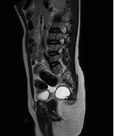

Рисунок 2.

МРТ крестцово-копчиковой области — переднее менингоцеле с множественными разнокалиберными кистами и стромальным компонентом

Figure 2.

MRI of the sacrococcygeal region — anterior meningocele with multiple cysts of different sizes and a stromal component